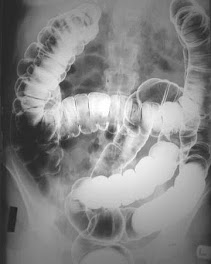

assisting in a barium study upper GI series